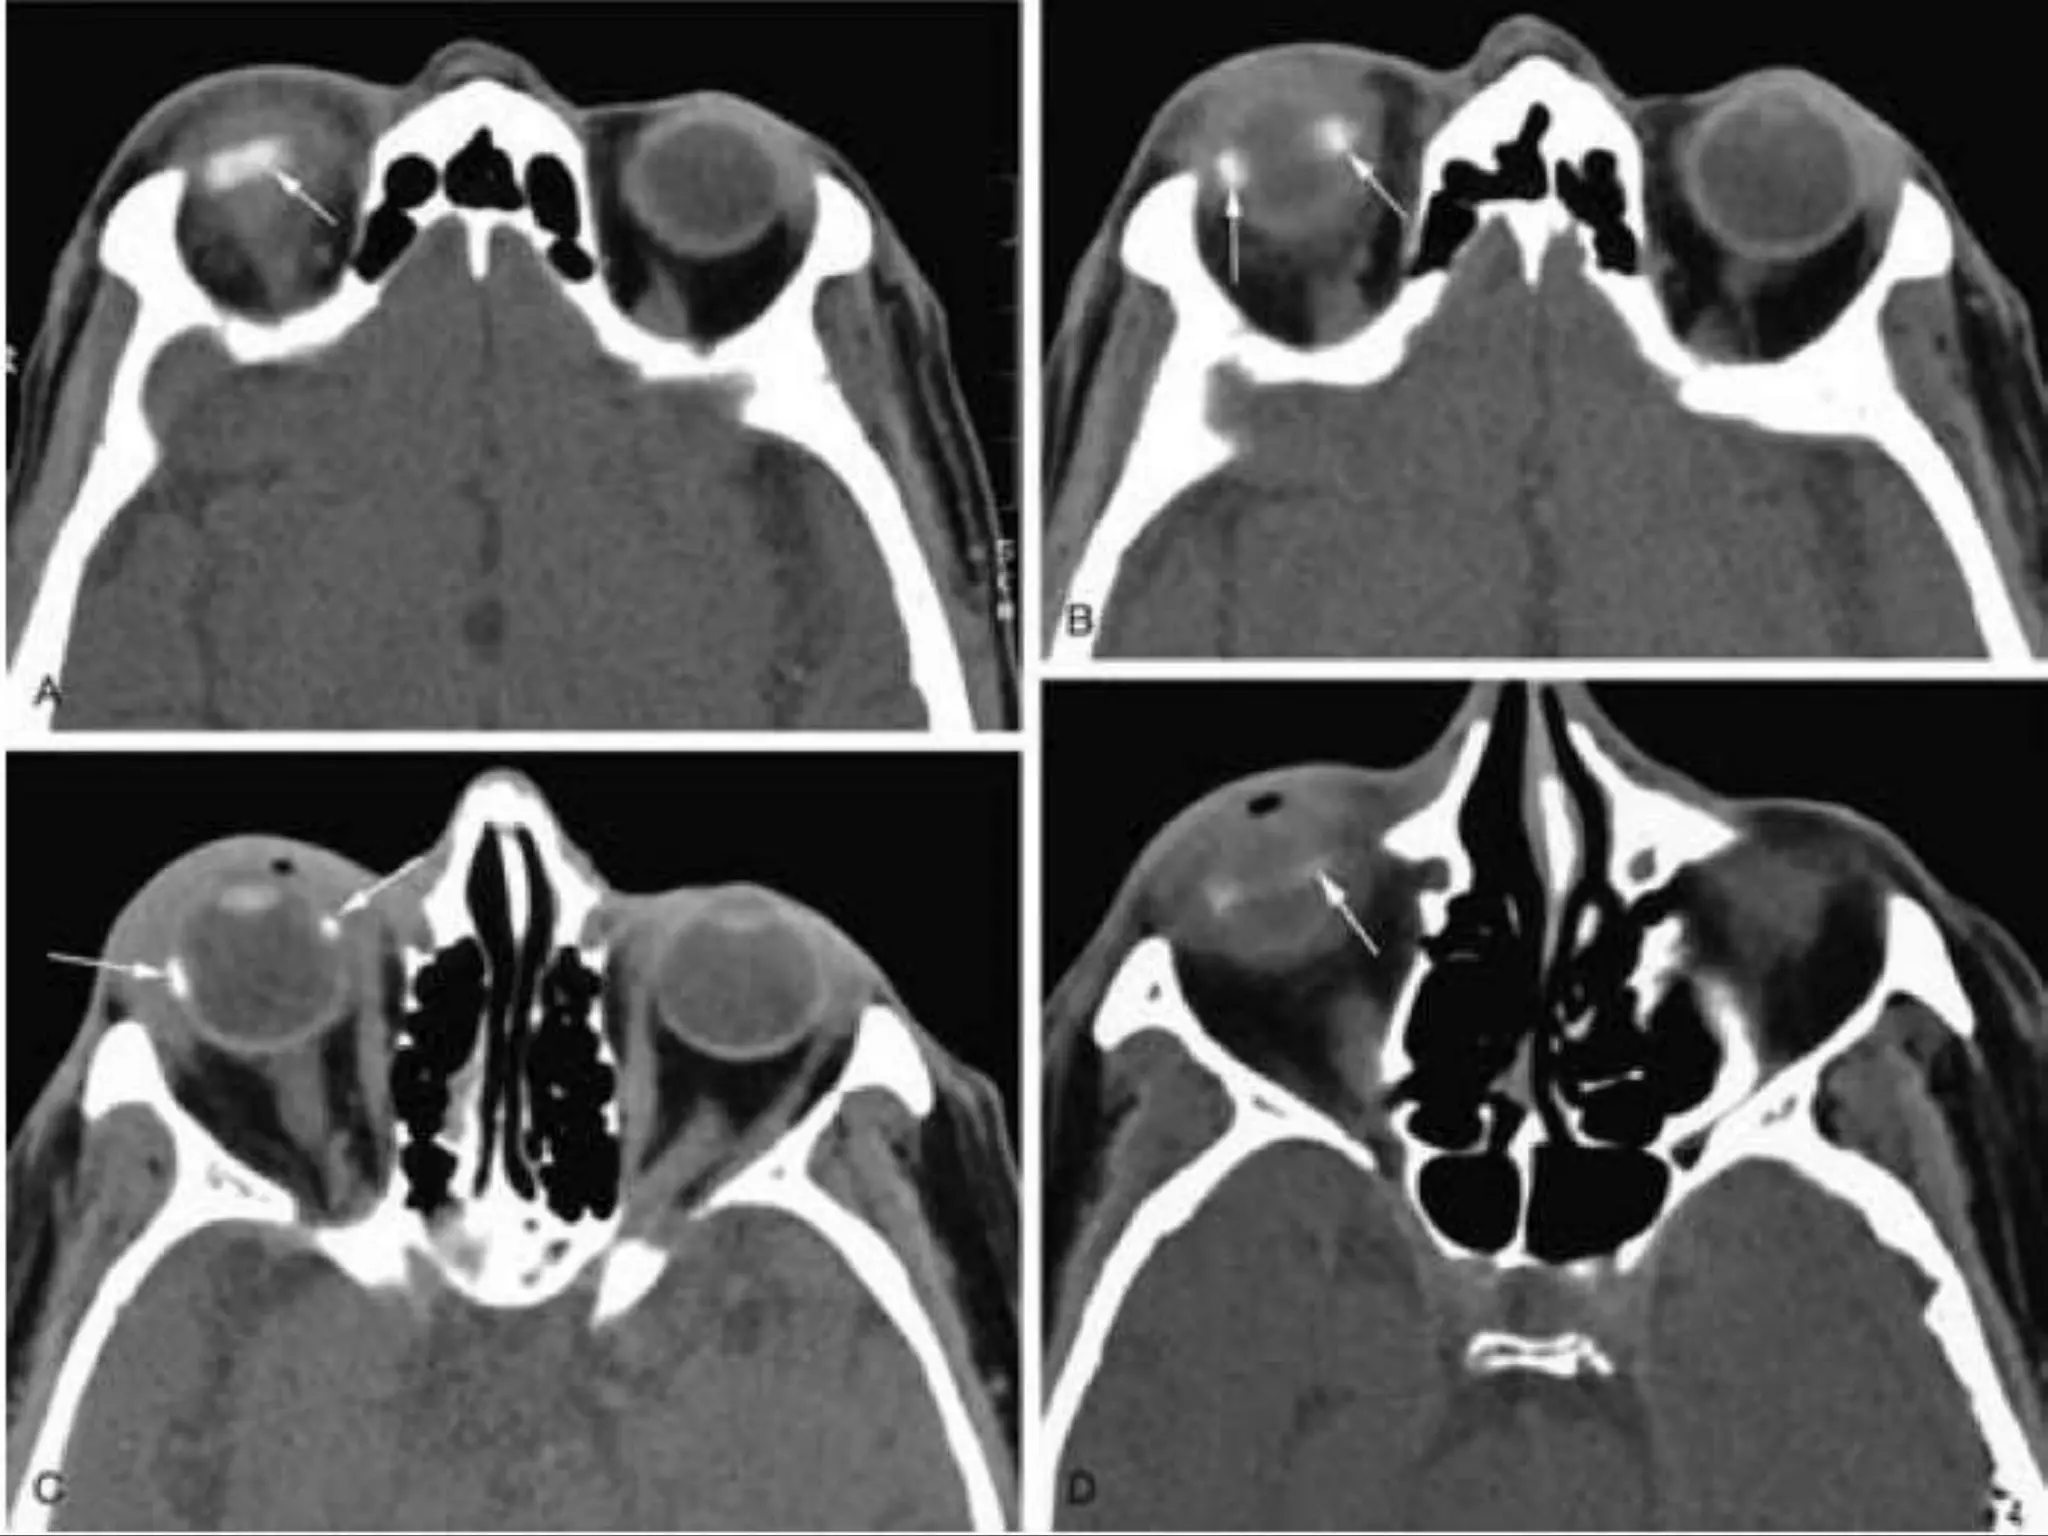

• #26 Retinoblastoma. A, Leukokoric left eye (whitish papillary reflex). B, Axial CT scan shows a large calcified intraocular mass (M). Note the noncalcified component (arrowhead). C, Axial T1WI shows a relatively hyperintense infiltrative mass (arrows). D, Axial T2WI shows a hypointense infiltrative mass (M). Note the extension along the temporal aspect of the globe (arrows).

• #27 Retinoblastoma with optic nerve involvement. A, Enhanced, fat-suppressed, axial T1-weighted MR image shows marked enhancement of a retinoblastoma (R) with extension into the optic nerve (arrow). B, Photomicrograph of an enucleated eye showing the tumor (T) as well as extension into the optic nerve head (arrow). (Courtesy of D. Ainbinder, MD, Tacoma, WA.)

• #28 Tetralateral retinoblastoma. A, Axial T2-weighted MR image shows bilateral retinoblastoma (arrows). B, Enhanced axial T1-weighted MR image shows a markedly enhancing suprasellar mass (m). Note the subarachnoid spread of the tumor, seen as leptomeningeal enhancement along the sylvian fissures (arrows). C, Enhanced axial T1-weighted MR image shows marked enhancement of a pinealoblastoma (arrow). D, Enhanced sagittal T1-weighted MR image obtained a few months later shows diffuse distal spinal cord (C ) and subarachnoid metastases (arrows).